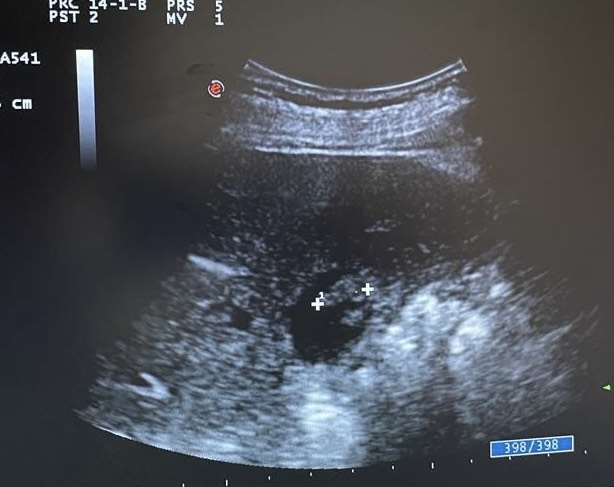

Mentalmente describí las lesiones,  se trata de lesiones múltiples hiperecogénicas  y adheridas a la pared vesicular y que no producen sombra posterior.

Confirmé que no se trataba de colelitiasis sino que en mi opinión eran múltiples pólipos vesiculares y alguno de ellos cercano a 1 cm de diámetro, sin poder descartar malignidad con la ecografía, por lo que solicité un TC abdominal que informó de un único pólipo vesicular de 6 mm.

Desde la consulta de cirugía se solicitó ecografía reglada y control en 6 meses que informó de múltiples engrosamientos nodulares en relación con pólipos (más de 10), los de mayor tamaño alcanzan 9 mm de grosor máximo. Alitiasica.